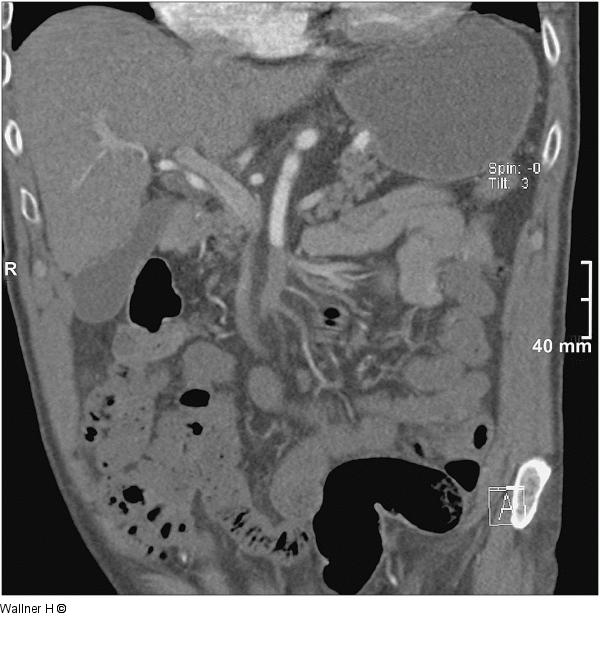

Abbildung 1: A. mesenterica superior Kontrasmittel NTCT mit Verschluss der A. mesenterica superior |

Abbildung 1: A. mesenterica superior

Kontrasmittel NTCT mit Verschluss der A. mesenterica superior |